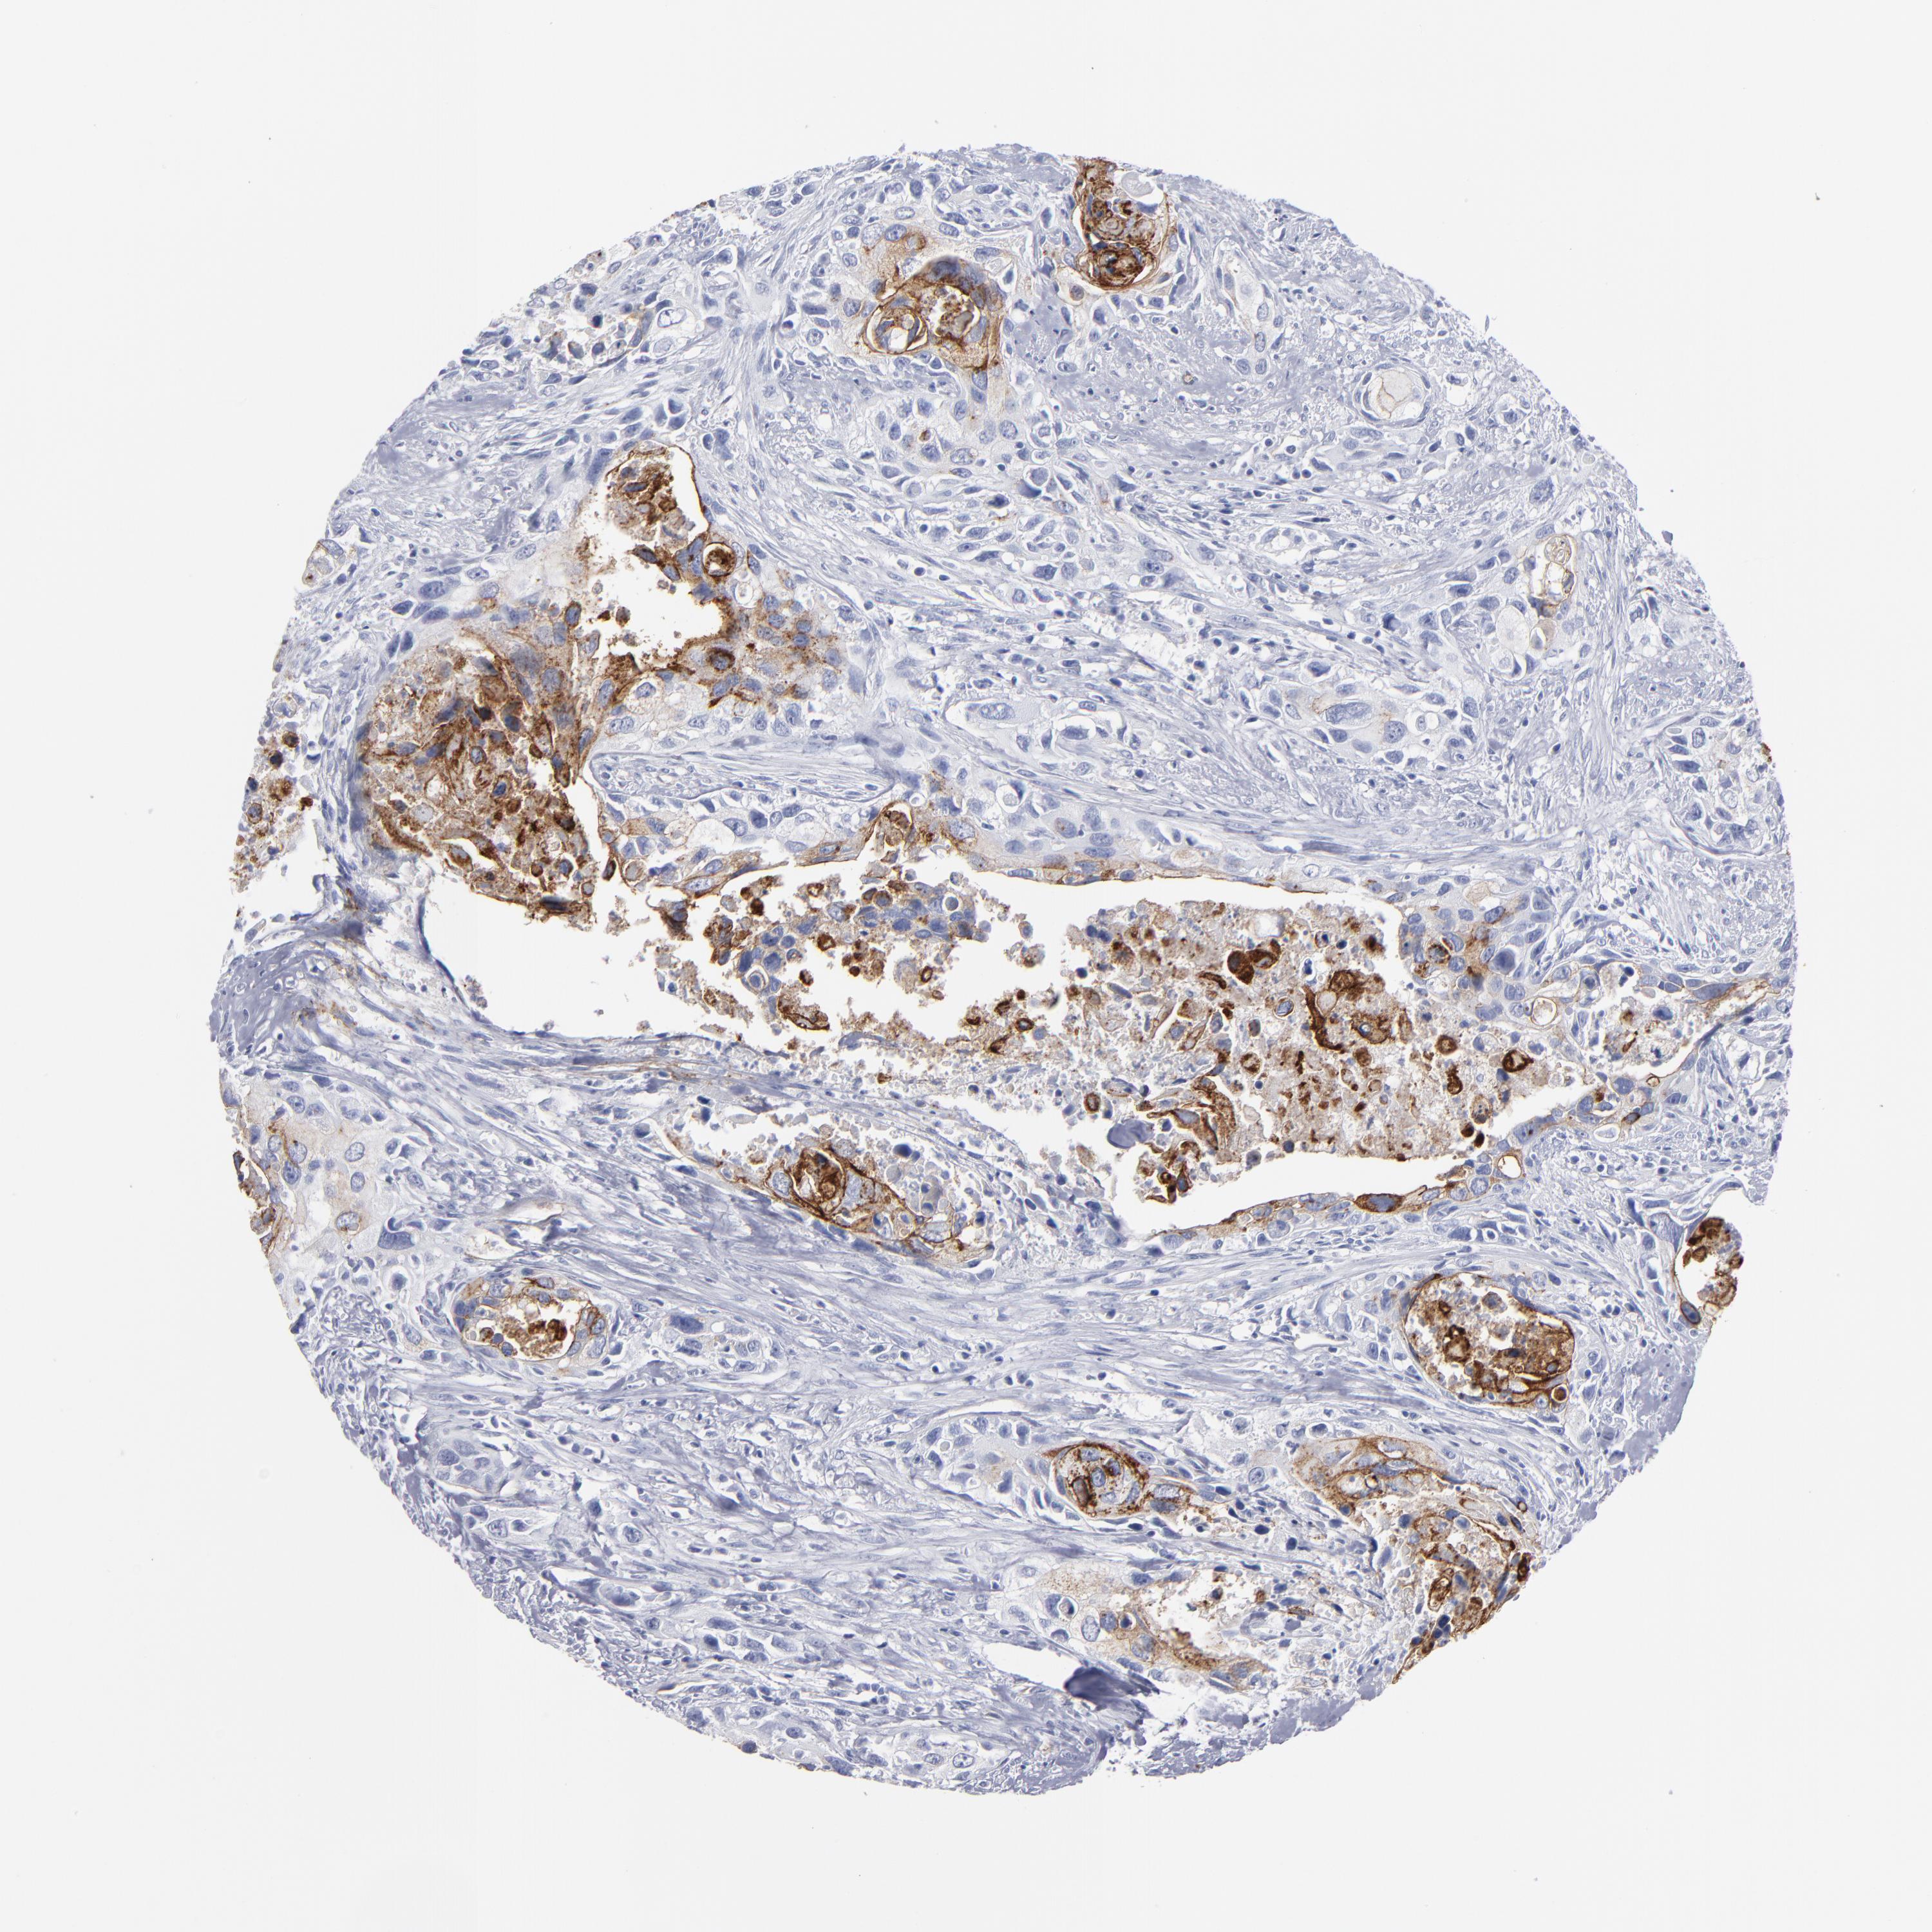

UROTHELIAL CANCER - Protein expressioni

A mouse-over function shows sample information and annotation data. Click on an image to view it in a full screen mode. Samples can be filtered based on level of antibody staining by selecting one or several of the following categories: high, medium, low and not detected. The assay and annotation is described here.

Antibody stainingi

Antibody staining in the annotated cell types in the current human tissue is reported as not detected, low, medium, or high, based on conventional immunohistochemistry profiling in selected tissues. This score is based on the combination of the staining intensity and fraction of stained cells.

Each image is clickable and will lead to virtual microscopy that enables deeper exploration of all samples and also displays staining intensity scores, fraction scores and subcellular localization as well as patient and tissue information for each sample.

Antibody HPA002823

Antibody CAB002760

Staining

High

Medium

Low

Not detected

Intensity

Strong

Moderate

Weak

Negative

Quantity

>75%

75%-25%

<25%

None

Location

Nuclear

Cytoplasmic/membranous

Cytoplasmic/membranous,nuclear

Urothelial carcinoma, High grade